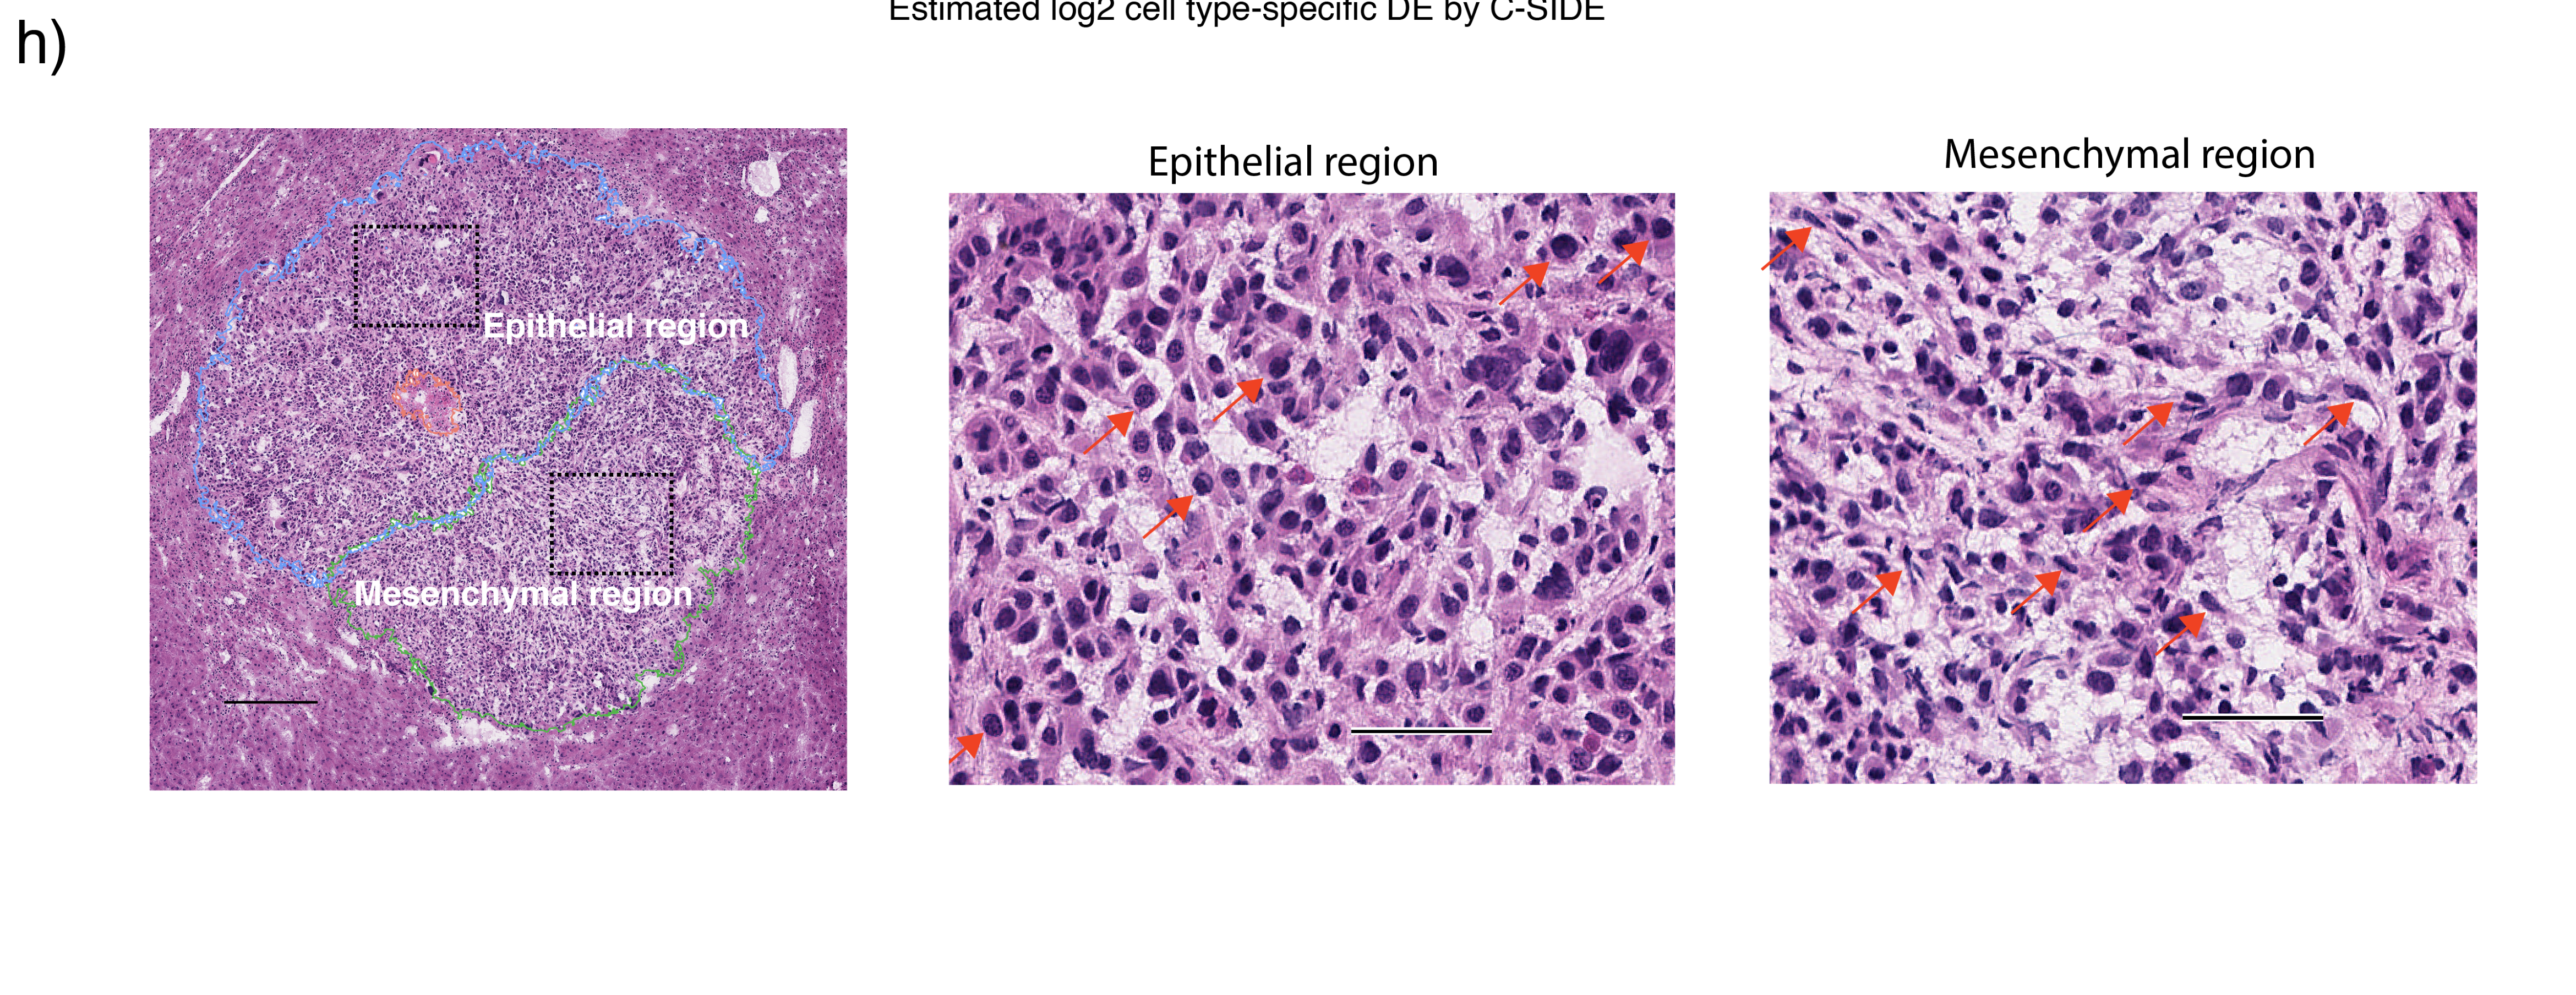

Cable D.M. et al. - 2022

Cell type-specific inference of differential expression in spatial transcriptomics

Condition Dimension

N/A

Data Components

Biological Annotation

Data

Metadata

None

Modality

Sequencing-based

Resolution of observation

Cellular

Visualized Elements

Observation

Do cells of a specific type show higher gene expression in regions of high pathological burden?

Biological

Cellular

Abstraction

Partial

Communicative/Contextualization

None

Comparative Design

None

Layout

Spatial : Physical

Scalability Strategy

None (Item-level)